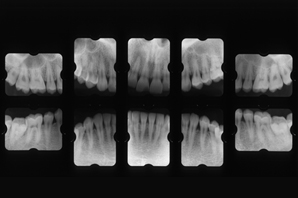

全部の歯のレントゲンを撮影します。歯周病はそれぞれの歯により症状、病態が違うためです。大きなレントゲンでは細部まで見えにくいためフロンティア歯科クリニックでは小さいレントゲンで撮影させてもらいます。